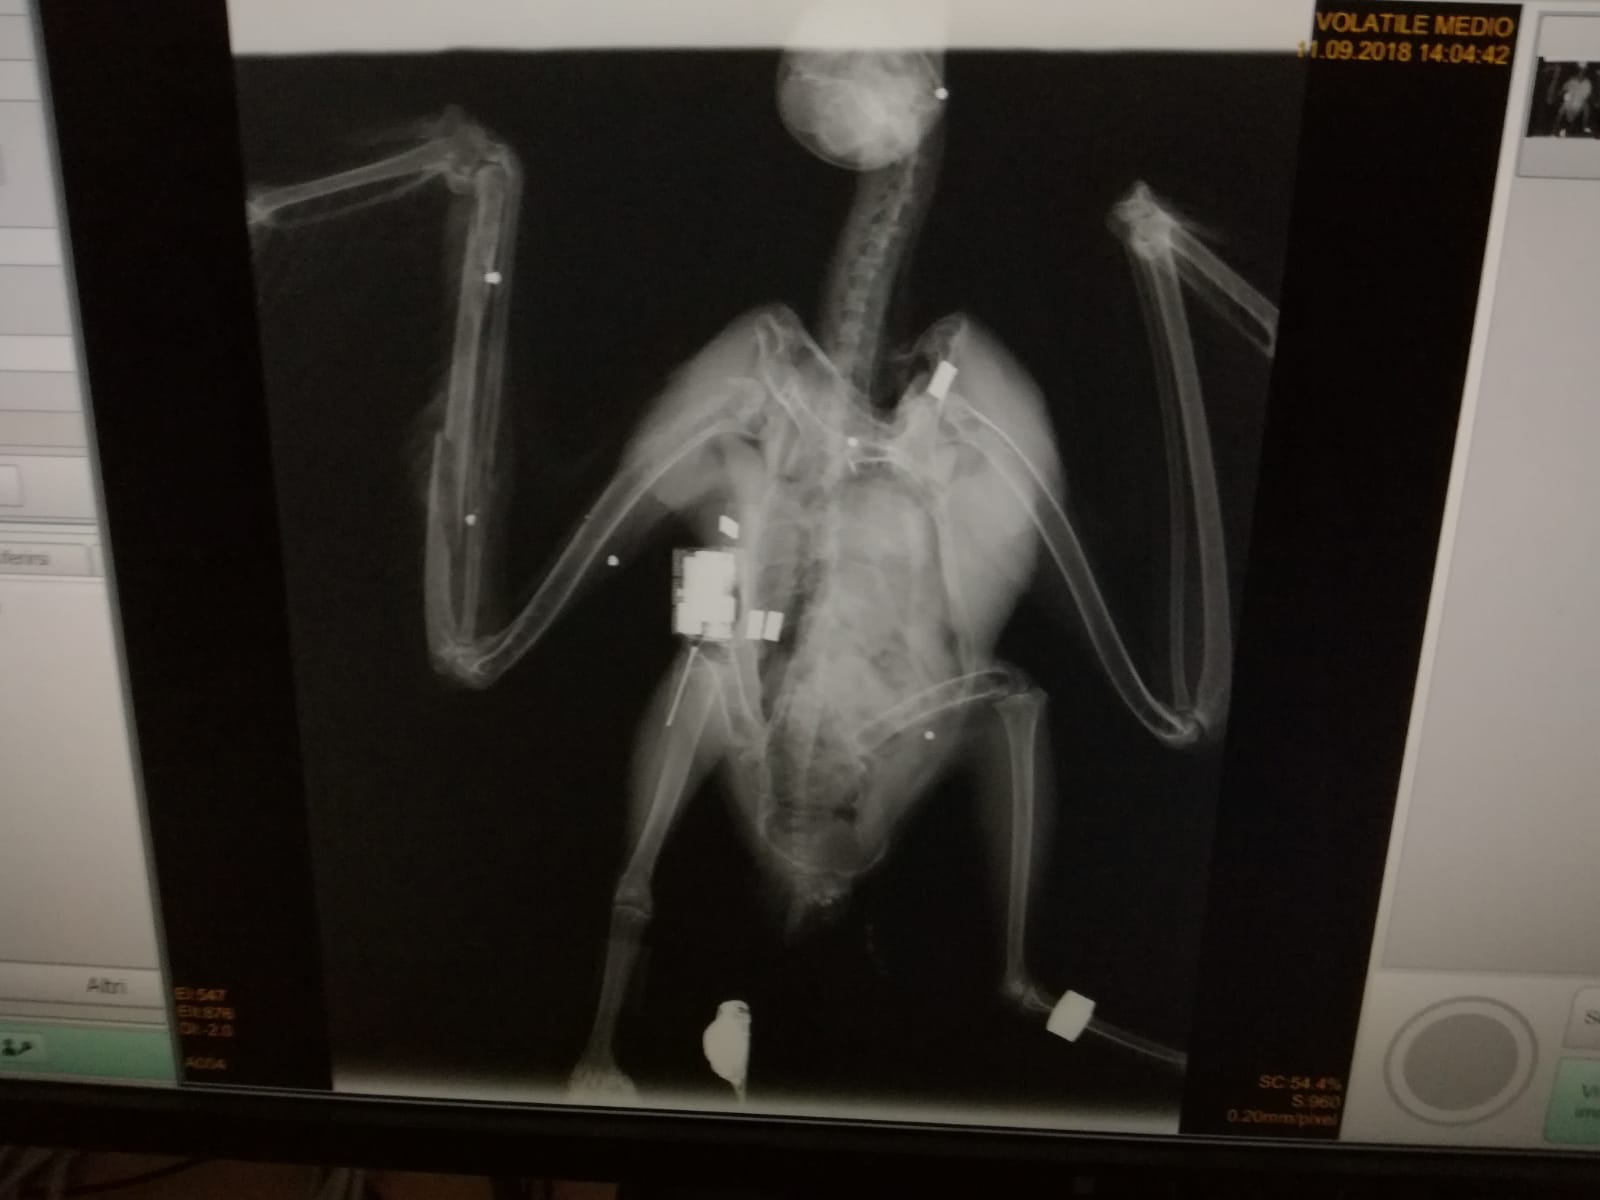

Home 8) Radiografia Clara.jpg